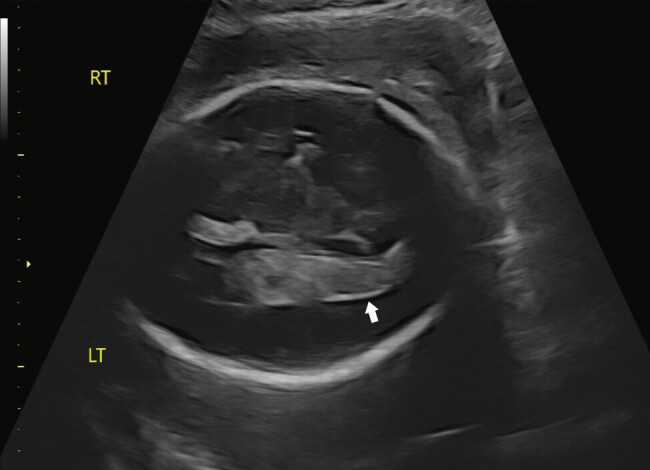

脑室内出血(IVH)是先天性巨细胞病毒(CMV)感染的罕见表现。我们报告一例原发性巨细胞病毒感染与早产以及胎儿贫血、血小板减少症和IVH相关。超声检查发现原因不明的IVH为先天性感染的检查提供了指示。我们的病例表明,在妊娠合并早产时需要详细的超声成像,因为超声诊断的整合可以显著影响管理并改善围产期结局。

Intraventricular hemorrhage (IVH) is an uncommon manifestation of congenital cytomegalovirus (CMV) infection. We report a case of primary CMV infection associated with preterm labor as well as fetal anemia, thrombocytopenia, and IVH. The finding of unexplained IVH on ultrasound provided an indication for testing of congenital infection. Our case indicates the need for detailed sonographic imaging in pregnancies complicated by preterm labor, as the integration of ultrasound diagnosis can significantly impact management and improve perinatal outcomes.